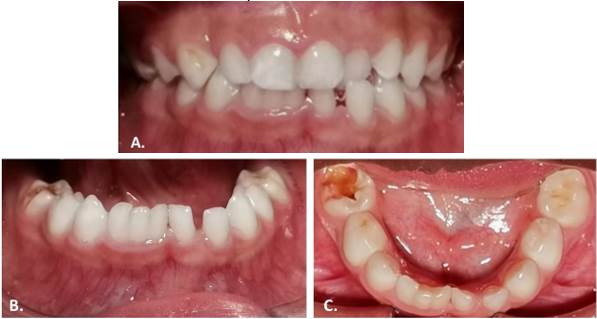

Al examen clínico intraoral, con espejo bucal y luz artificial en el sillón dental se destaca la presencia de dentición primaria con acúmulo de biofilme, lesiones cariosas cavitadas en molares primarios, la presencia de dos dientes supernumerarios: uno en el sector anterosuperior izquierdo y otro en el sector anteroinferior, fusionado con el incisivo central y el lateral derecho con dos surcos verticales en la superficie labial y lingual en la unión de las piezas dentales, sin presencia de lesiones cariosas y con un periodonto circundante sano. En la sección anterior superior se presenta mordida cruzada anterior de una pieza dental y a nivel de mandíbula se observó leve giroversión del central primario izquierdo y de las piezas fusionadas (Figura 1 A, B y C).